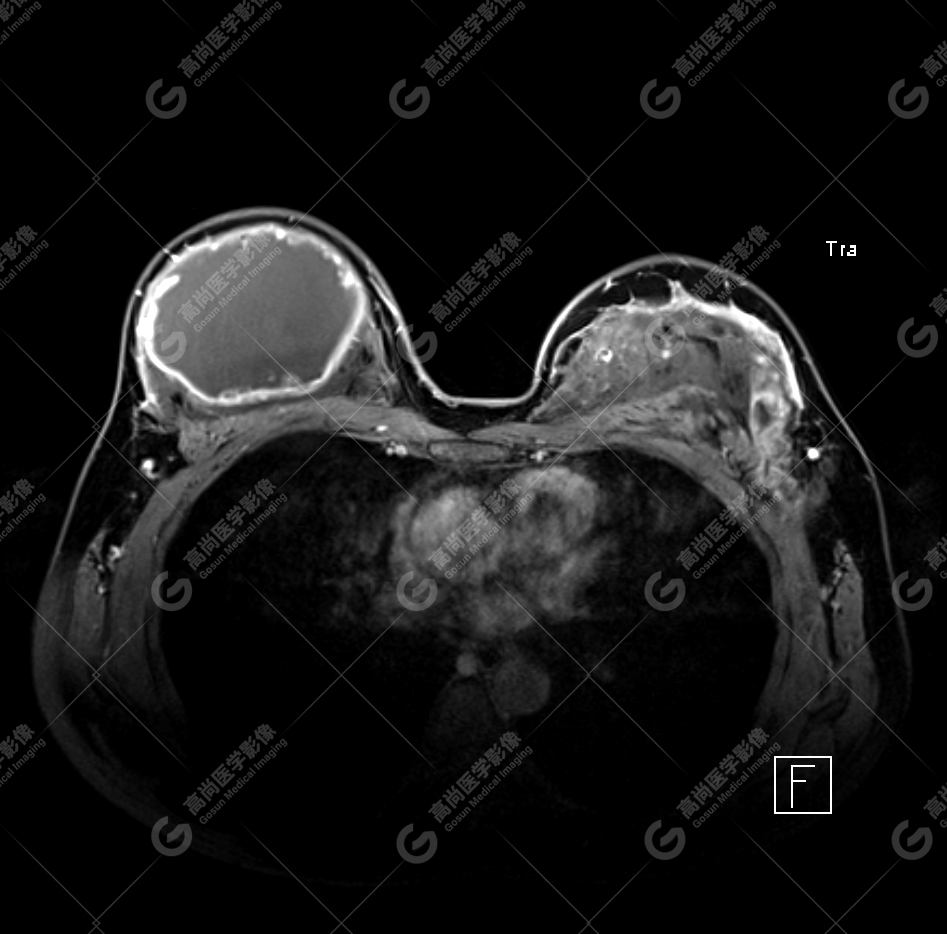

病例 4:乳腺注射物部分取出术后,后硅胶假体植入术后 3 年余

双侧假体包膜不光整,包膜下可见多发线样低信号影,左侧假体内可见「面条征」——双侧假体内包膜破裂(部分破裂)